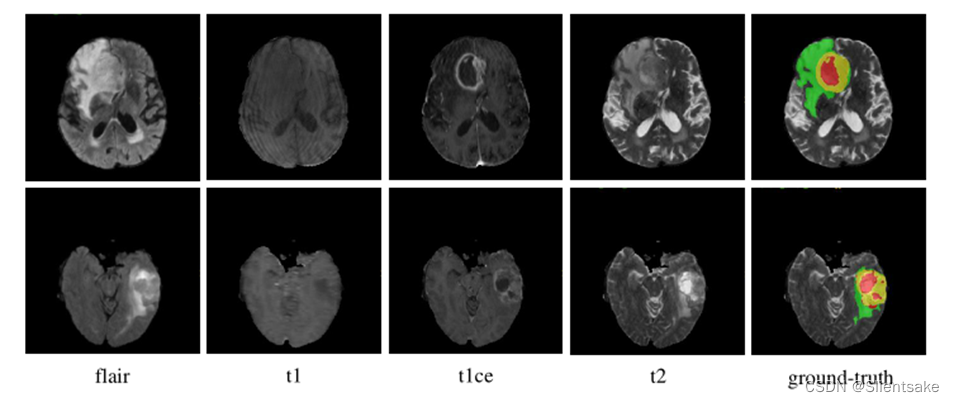

图1所示。示例扫描所有的模式,并附上相应的基本事实。NCR/NET、ED和ET区域分别用红色、绿色和黄色表示。

BraTS挑战赛庆祝了10周年,由北美放射学会(RSNA)、美国神经放射学会(ASNR)和医学图像计算和计算机辅助干预学会(MICCAI)共同组织。BraTS21数据集包含2000个多模态脑MR研究(8000个mpMRI扫描),包括1521个训练、219个验证和260个测试案例。与前几年挑战的数据设置相同,每项研究有4张MR图像,分别为T1加权(T1)、对比度后T1加权(T1ce)、T2加权(T2)和液体衰减反演恢复(Flair)序列,如图1所示。所有MR图像的尺寸均为240 × 240 × 155,体素间距均为1 × 1 × 1mm3。对于每一项研究,专家都将肿瘤增强(ET)、瘤周水肿(ED)、坏死和非增强肿瘤核心(NCR/NET)按体素逐个进行标注。培训研究的注释是公开的,而验证研究和测试研究的注释将被保留,分别用于在线评估和最终细分竞争。